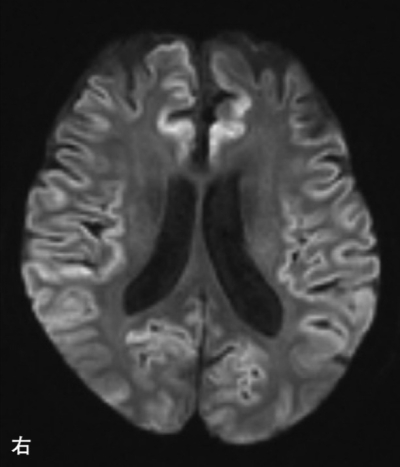

血液所見:赤血球 398 万、白血球 6,500。血液生化学所見:血糖 179 mg/dL、HbA1c 8.2 %(基準 4.6〜6.2)。免疫血清学所見:CRP 4.3 mg/dL、Tリンパ球 CD4/CD8 比 1.9(基準 0.6〜2.9)、β-D-グルカン 5.0 pg/mL(基準 10以下)。ツベルクリン反応陰性。脳脊髄液所見:初圧 320 mmH2O 基準 70〜170)、細胞数 86/mm3 (基準0〜2) (単核球 58、多形核球 28)、蛋白 195 mg/dL(基準15〜45)、糖 3 mg/dL(基準 50〜75)。脳脊髄液の細胞診は陰性。脳脊髄液の染色標本、肺野条件の胸部CT及び頭部MRI の拡散強調像を別に示す。